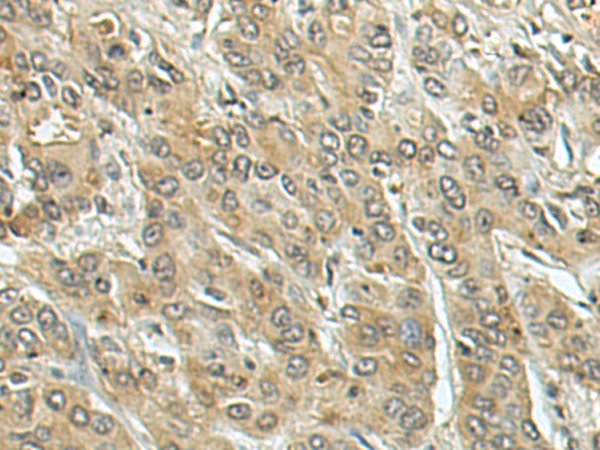

IHC positive control: |

Human liver cancer |

IHC Recommend dilution: |

250-500 |